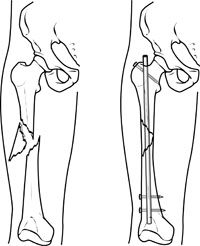

In cases where the skin and other soft tissues around the fracture are badly damaged, an external fixator may be applied until surgery can be tolerated.During this operation, the bone fragments are first repositioned (reduced) in their normal alignment, and then held together with special screws or by attaching metal plates to the outer surface of the bone. The fragments may also be held together by inserting rods down through the marrow space in the center of the bone.

A specially designed metal rod, called an intramedullary nail, provides strong fixation for this thighbone fracture.